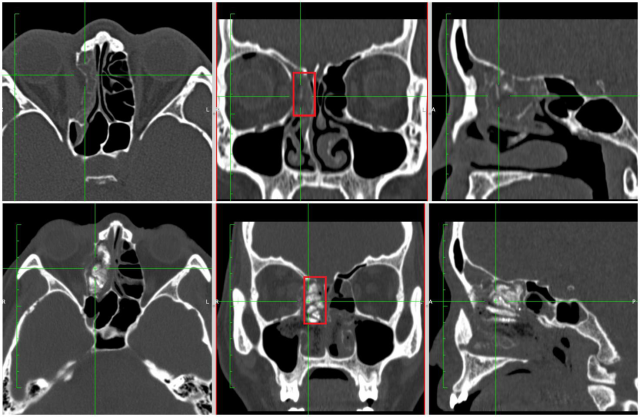

图为鼻内镜微创复位手术前后对比照,下图红框内为支撑物

针对刘女士的情况,吴彦桥通过鼻内镜将骨折的眶壁连同其疝入的筛窦一同复位,以粉碎的眶壁、脂肪和内直肌保护视神经,放入碘仿纱条填塞支撑,术后两个月再取出,实现了从内向外复位,避免了损伤视神经的风险,同时眼周围无手术切口,值得一提的是该手术方法利用价廉的碘纺纱进行暂时性填充,大大降低了患者的手术费用。